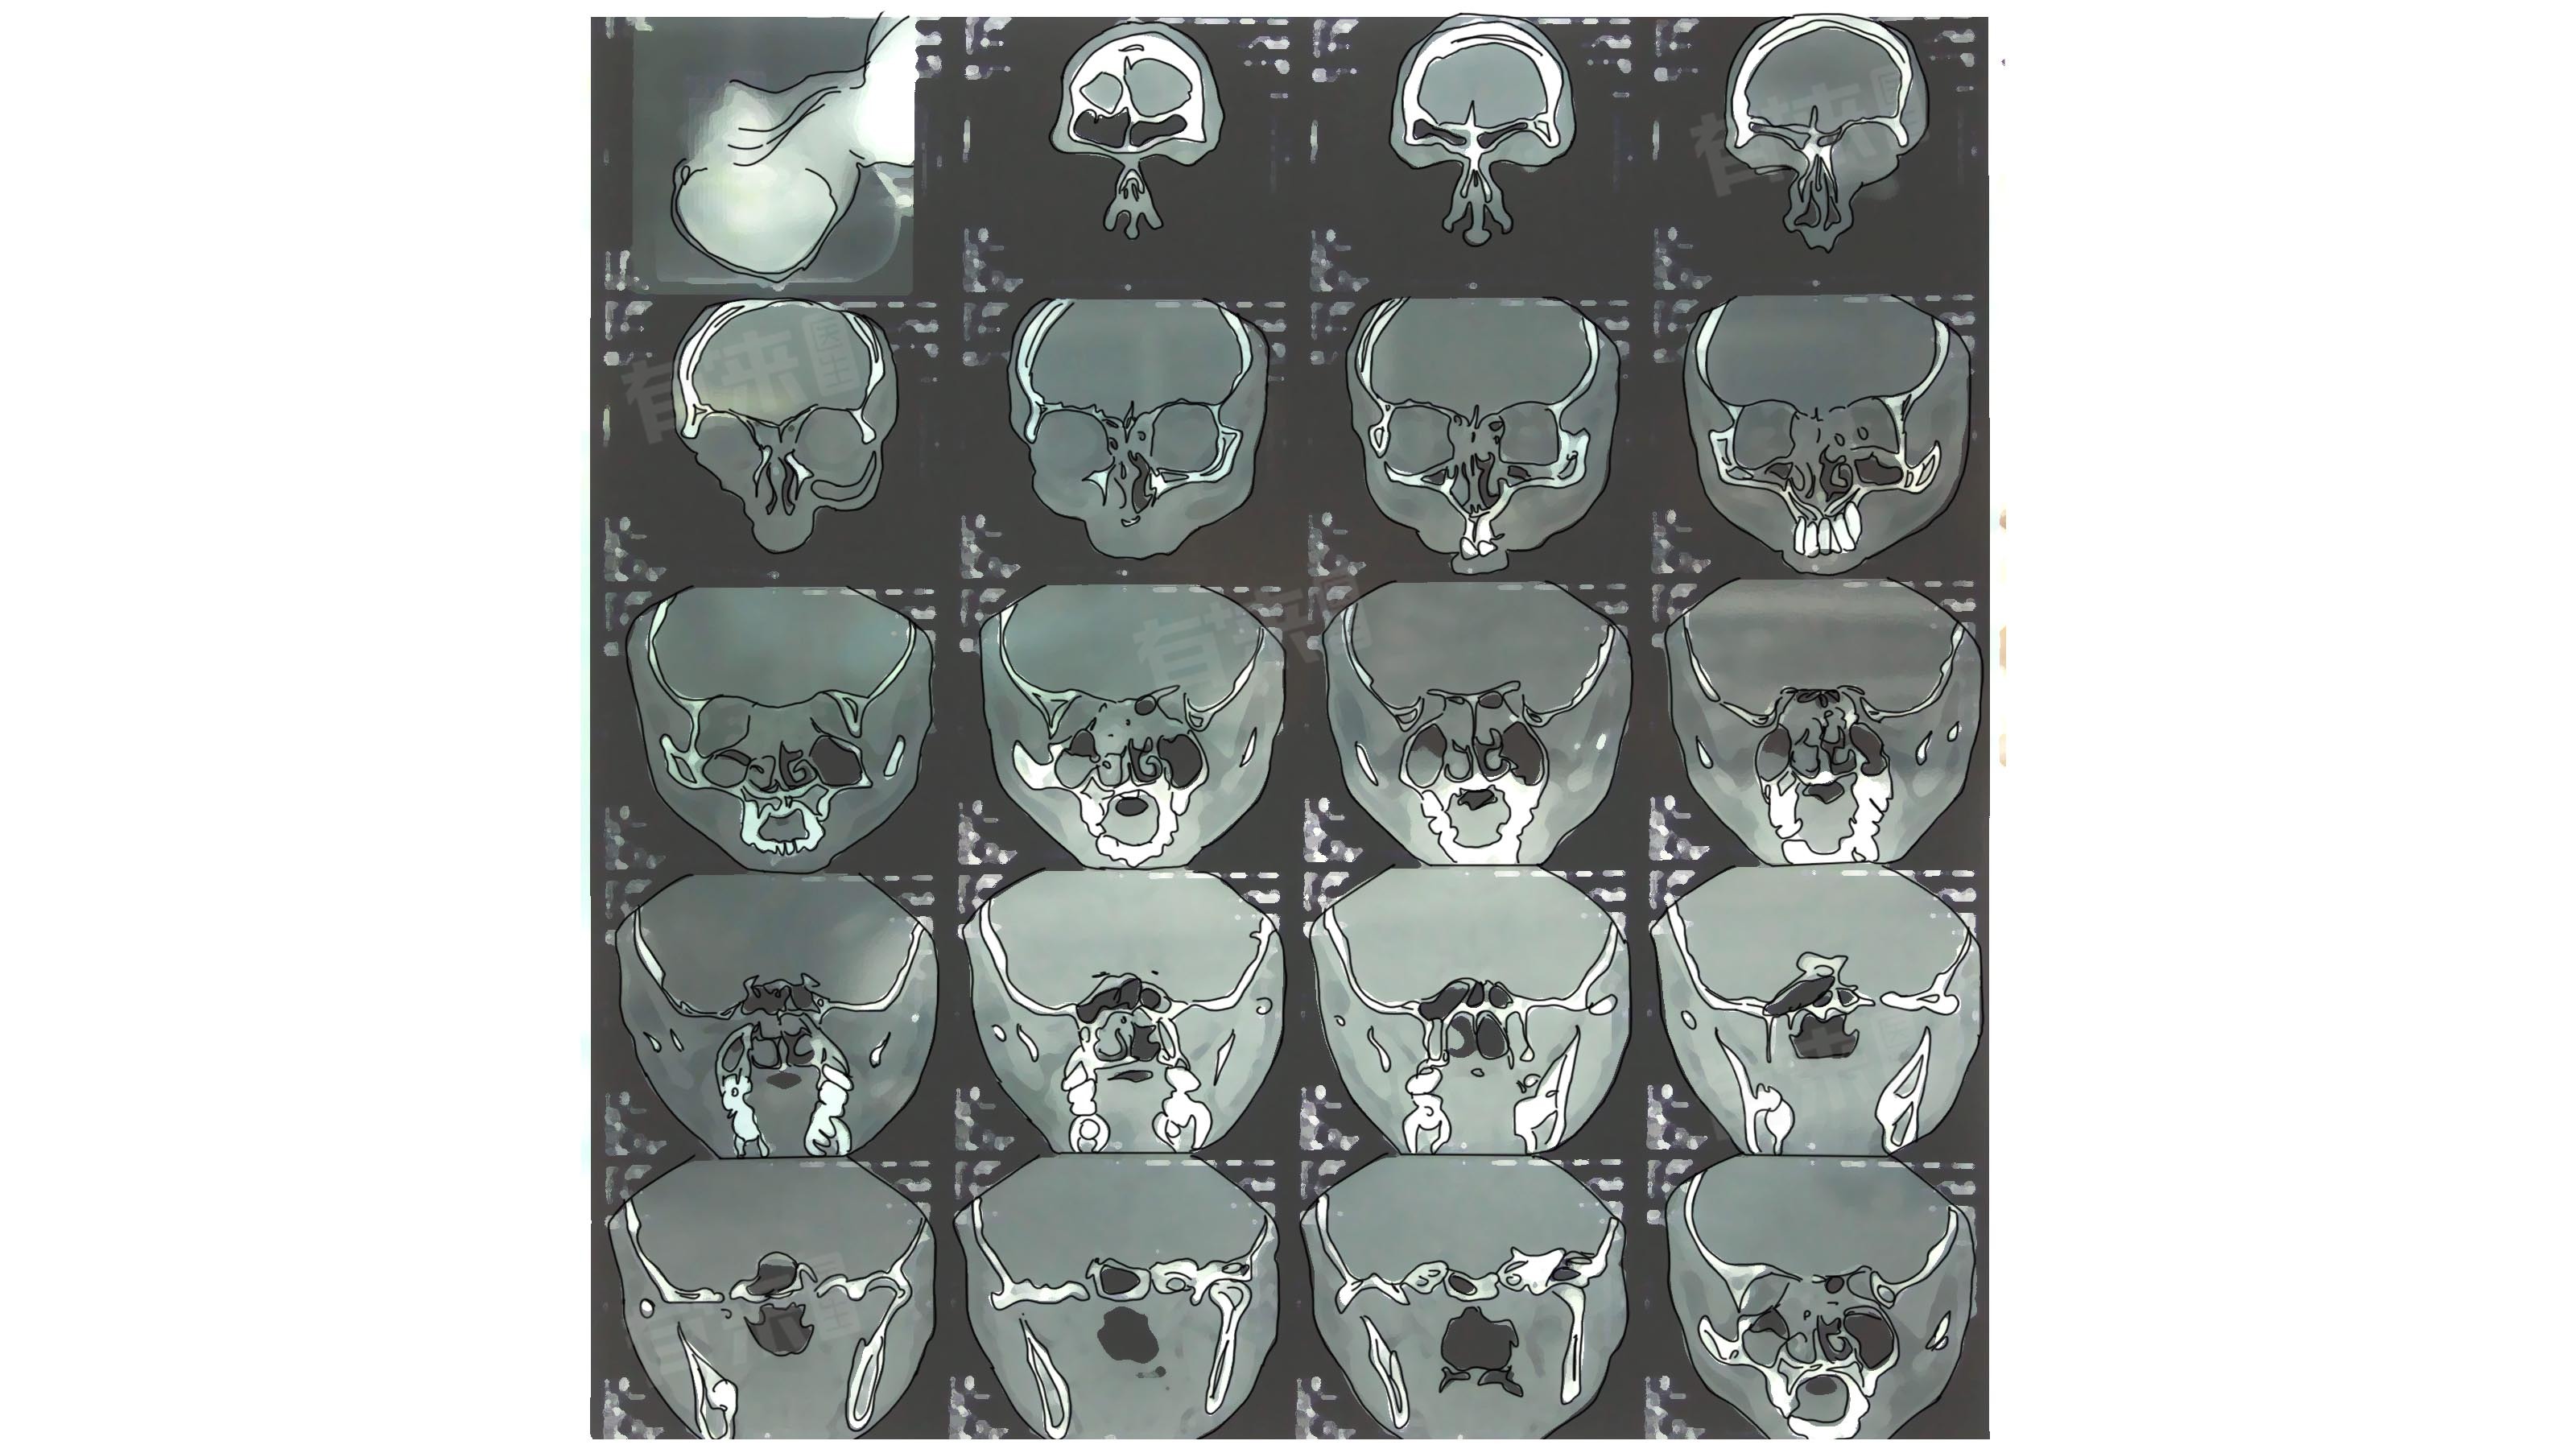

鼻窦CT的作用

1、清晰呈现鼻窦的解剖结构:像上颌窦、筛窦、额窦、蝶窦等各个鼻窦的形态、大小以及它们之间的相互关系都能一目了然,帮助医生准确判断鼻窦是否存在先天性发育异常的情况。

2、帮助诊断鼻窦炎:能清楚显示鼻窦内黏膜的增厚程度、有无积液、积脓等炎性改变,为后续制定合理的治疗方案提供依据。

3、排查鼻窦肿瘤:可以发现鼻窦内是否存在占位性病变,并且能进一步观察病变的大小、位置、边界等情况,辅助鉴别肿瘤是良性还是恶性,有助于尽早安排针对性的诊疗措施。